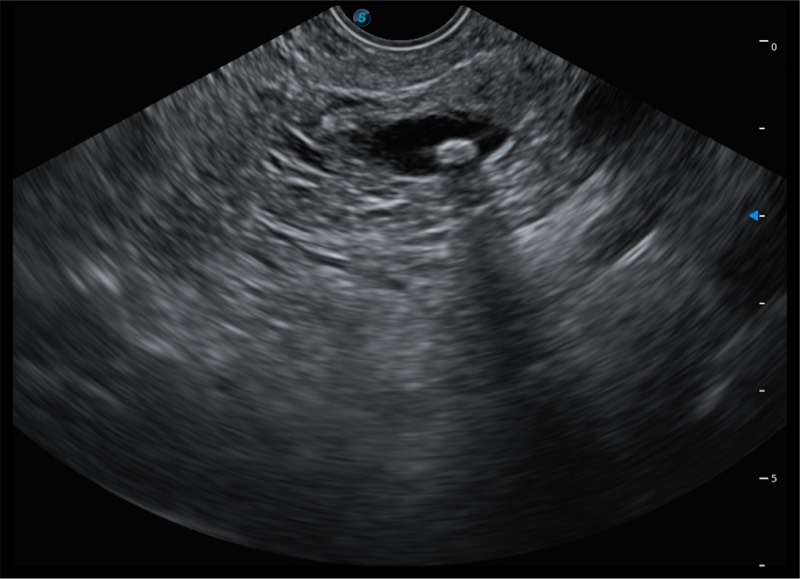

搭载百万级CMOS成像技术

及自主研发凸阵换能器,

可呈现优质的内镜和超声画面

4.0mm大钳道

12.6mm先端部外径

150°超声扫描角度